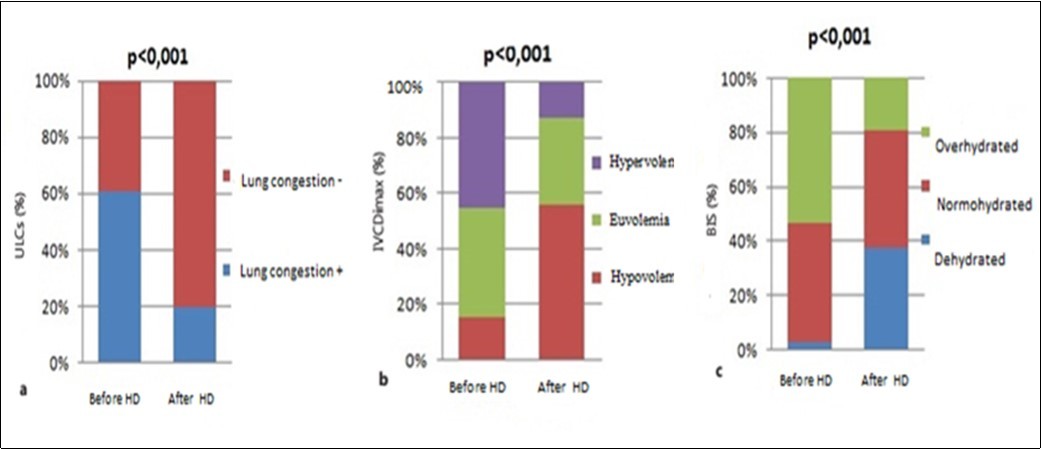

After hemodialysis sessions, according to the number of B-lines, 20% of patients were able to have lung congestion, and according to fluid status determined by bioimpedance spectroscopy also 20% of patients were able to be overhydrated. However there were more patients who were classified hypovolemic by ultrasound of the IVC (57%) than by impedance (38%) (Figure 2).

Figure 2.Distribution of groups according to fluid status determined by lung ultrasound comets (a), inferior vena cava diameter (b), bioimpedance spectroscopy (c), before and after hemodialysis session